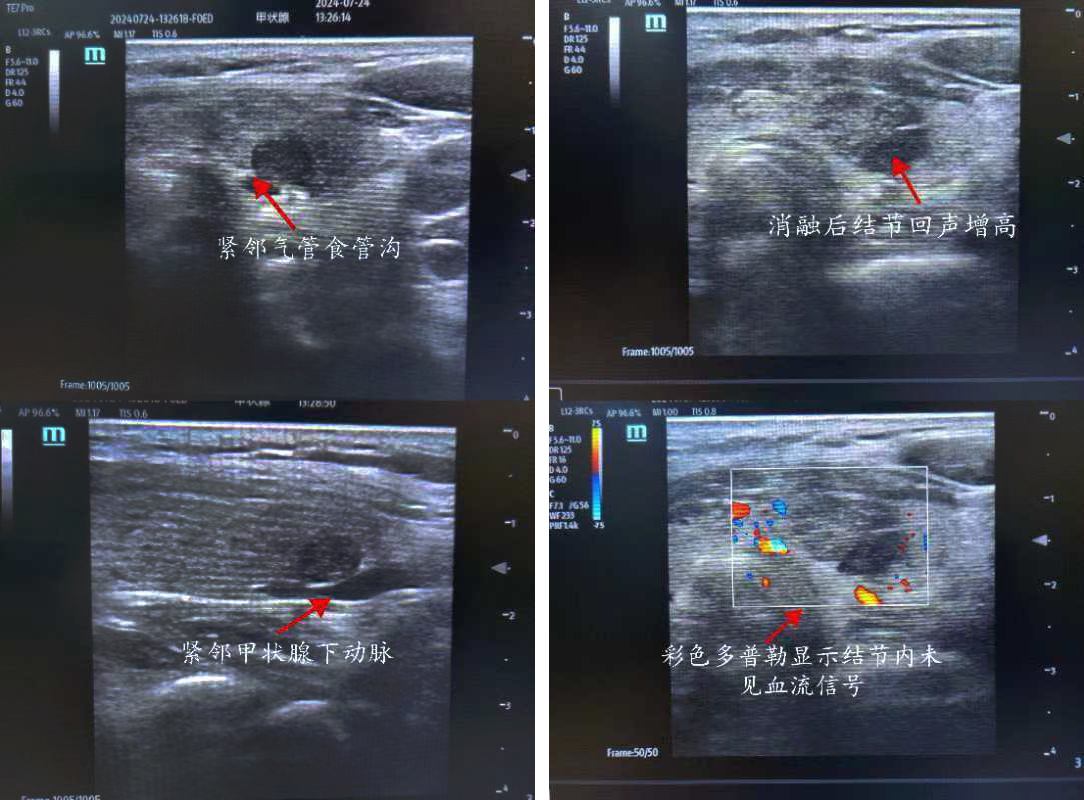

患者,女,50歲,甲狀腺彩超示:甲狀腺左側葉下極探及一約0.8*0.3cm低回聲結節(jié),界尚清,形態(tài)不規(guī)則,內回聲不均質,內似可見點狀強回聲,周邊及其內可見血流信號 TI-RADS 4a級。入院后行甲狀腺左側葉結節(jié)細針穿刺細胞學檢查+BRAF基因檢測,結果示:考慮為濾泡上皮細胞非典型病變,BRAFV600E基因檢測未見突變。但患者左側葉4a結節(jié)位于腺體背側,緊鄰氣管食管溝,與左側喉返神經走行位置相近,患者自覺復查隨訪心理壓力大,強烈要求積極處理此結節(jié)。但因傳統手術切除治療創(chuàng)傷較大,美觀性較差,且術后可能需終身服藥,患者不愿接受手術切除。

俞景奎主任醫(yī)師、孫守毅副主任醫(yī)師及診療組詳細分析討論后,決定為患者行超聲引導下甲狀腺左葉結節(jié)微波消融術。對于該患者而言,行微波消融治療有兩大難點,一是患者左葉結節(jié)位于腺體背側,緊鄰左側喉返神經,消融治療易損傷喉返神經致聲音嘶?。欢遣食乱娀颊咦笕~結節(jié)背側緊貼甲狀腺下動脈,易出現血管損傷出血情況。在李峰主任和俞景奎主任醫(yī)師支持指導下,孫守毅副主任醫(yī)師及馬凱麗主治醫(yī)師為患者制定詳細手術方案,術中在結節(jié)與周圍重要組織結構之間建立隔離帶,形成安全隔離區(qū)域,力爭將患者手術風險降到最低。最終,患者順利完成手術,且術后血管和喉返神經均無損傷,患者聲音無變化, 順利康復出院,對治療效果非常滿意。